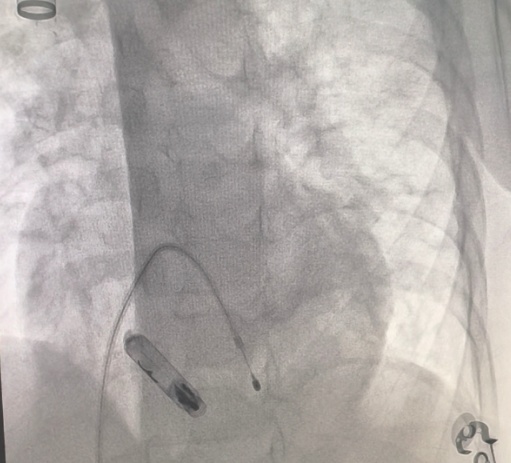

手术由广西医科大学第一附属医院儿科心血管团队核心专家庞玉生教授、陈成教授、覃素元教授、苏丹艳教授及外院李奋教授实施,在全麻下精准操作:超声引导下穿刺颈静脉建立通路,将仅重2.4克、体积堪比胶囊的AVEIR™ VR无导线起搏器,通过微创导管精准送达患儿右心室最佳起搏位点,独创主动螺旋固定技术实现稳妥锚定,术中实时测试起搏阈值、损伤电流、阻抗等关键参数均达理想标准,全程无血管损伤、心脏穿孔等并发症,手术顺利完成。

目前,患儿术后生命体征平稳,心率已恢复至正常范围,乏力症状明显改善,预计短期内即可康复出院,重返校园享受快乐童年。